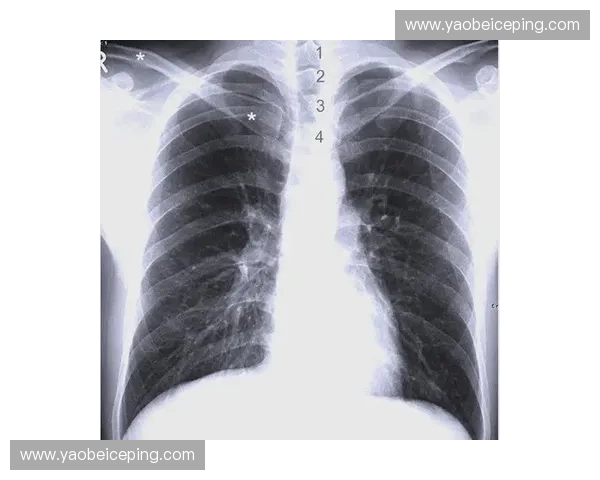

影像学技术,尤其是X线、CT(计算机断层扫描)和MRI(磁共振成像),在肋部渗透的诊断中发挥着关键作用。X线检查是最常用的初步诊断工具,能够帮助检测肋骨是否存在骨折及其错位情况。然而,X线对于软组织的显示能力有限,不能有效评估胸腔内脏器的损伤情况。

CT扫描在肋部渗透的诊断中具有更高的敏感性,尤其是在检测肋骨骨折、肺部损伤及气胸等方面表现尤为突出。通过CT扫描可以清楚地看到肋骨周围的骨折情况及可能存在的软组织损伤,有助于医生制定具体的治疗方案。